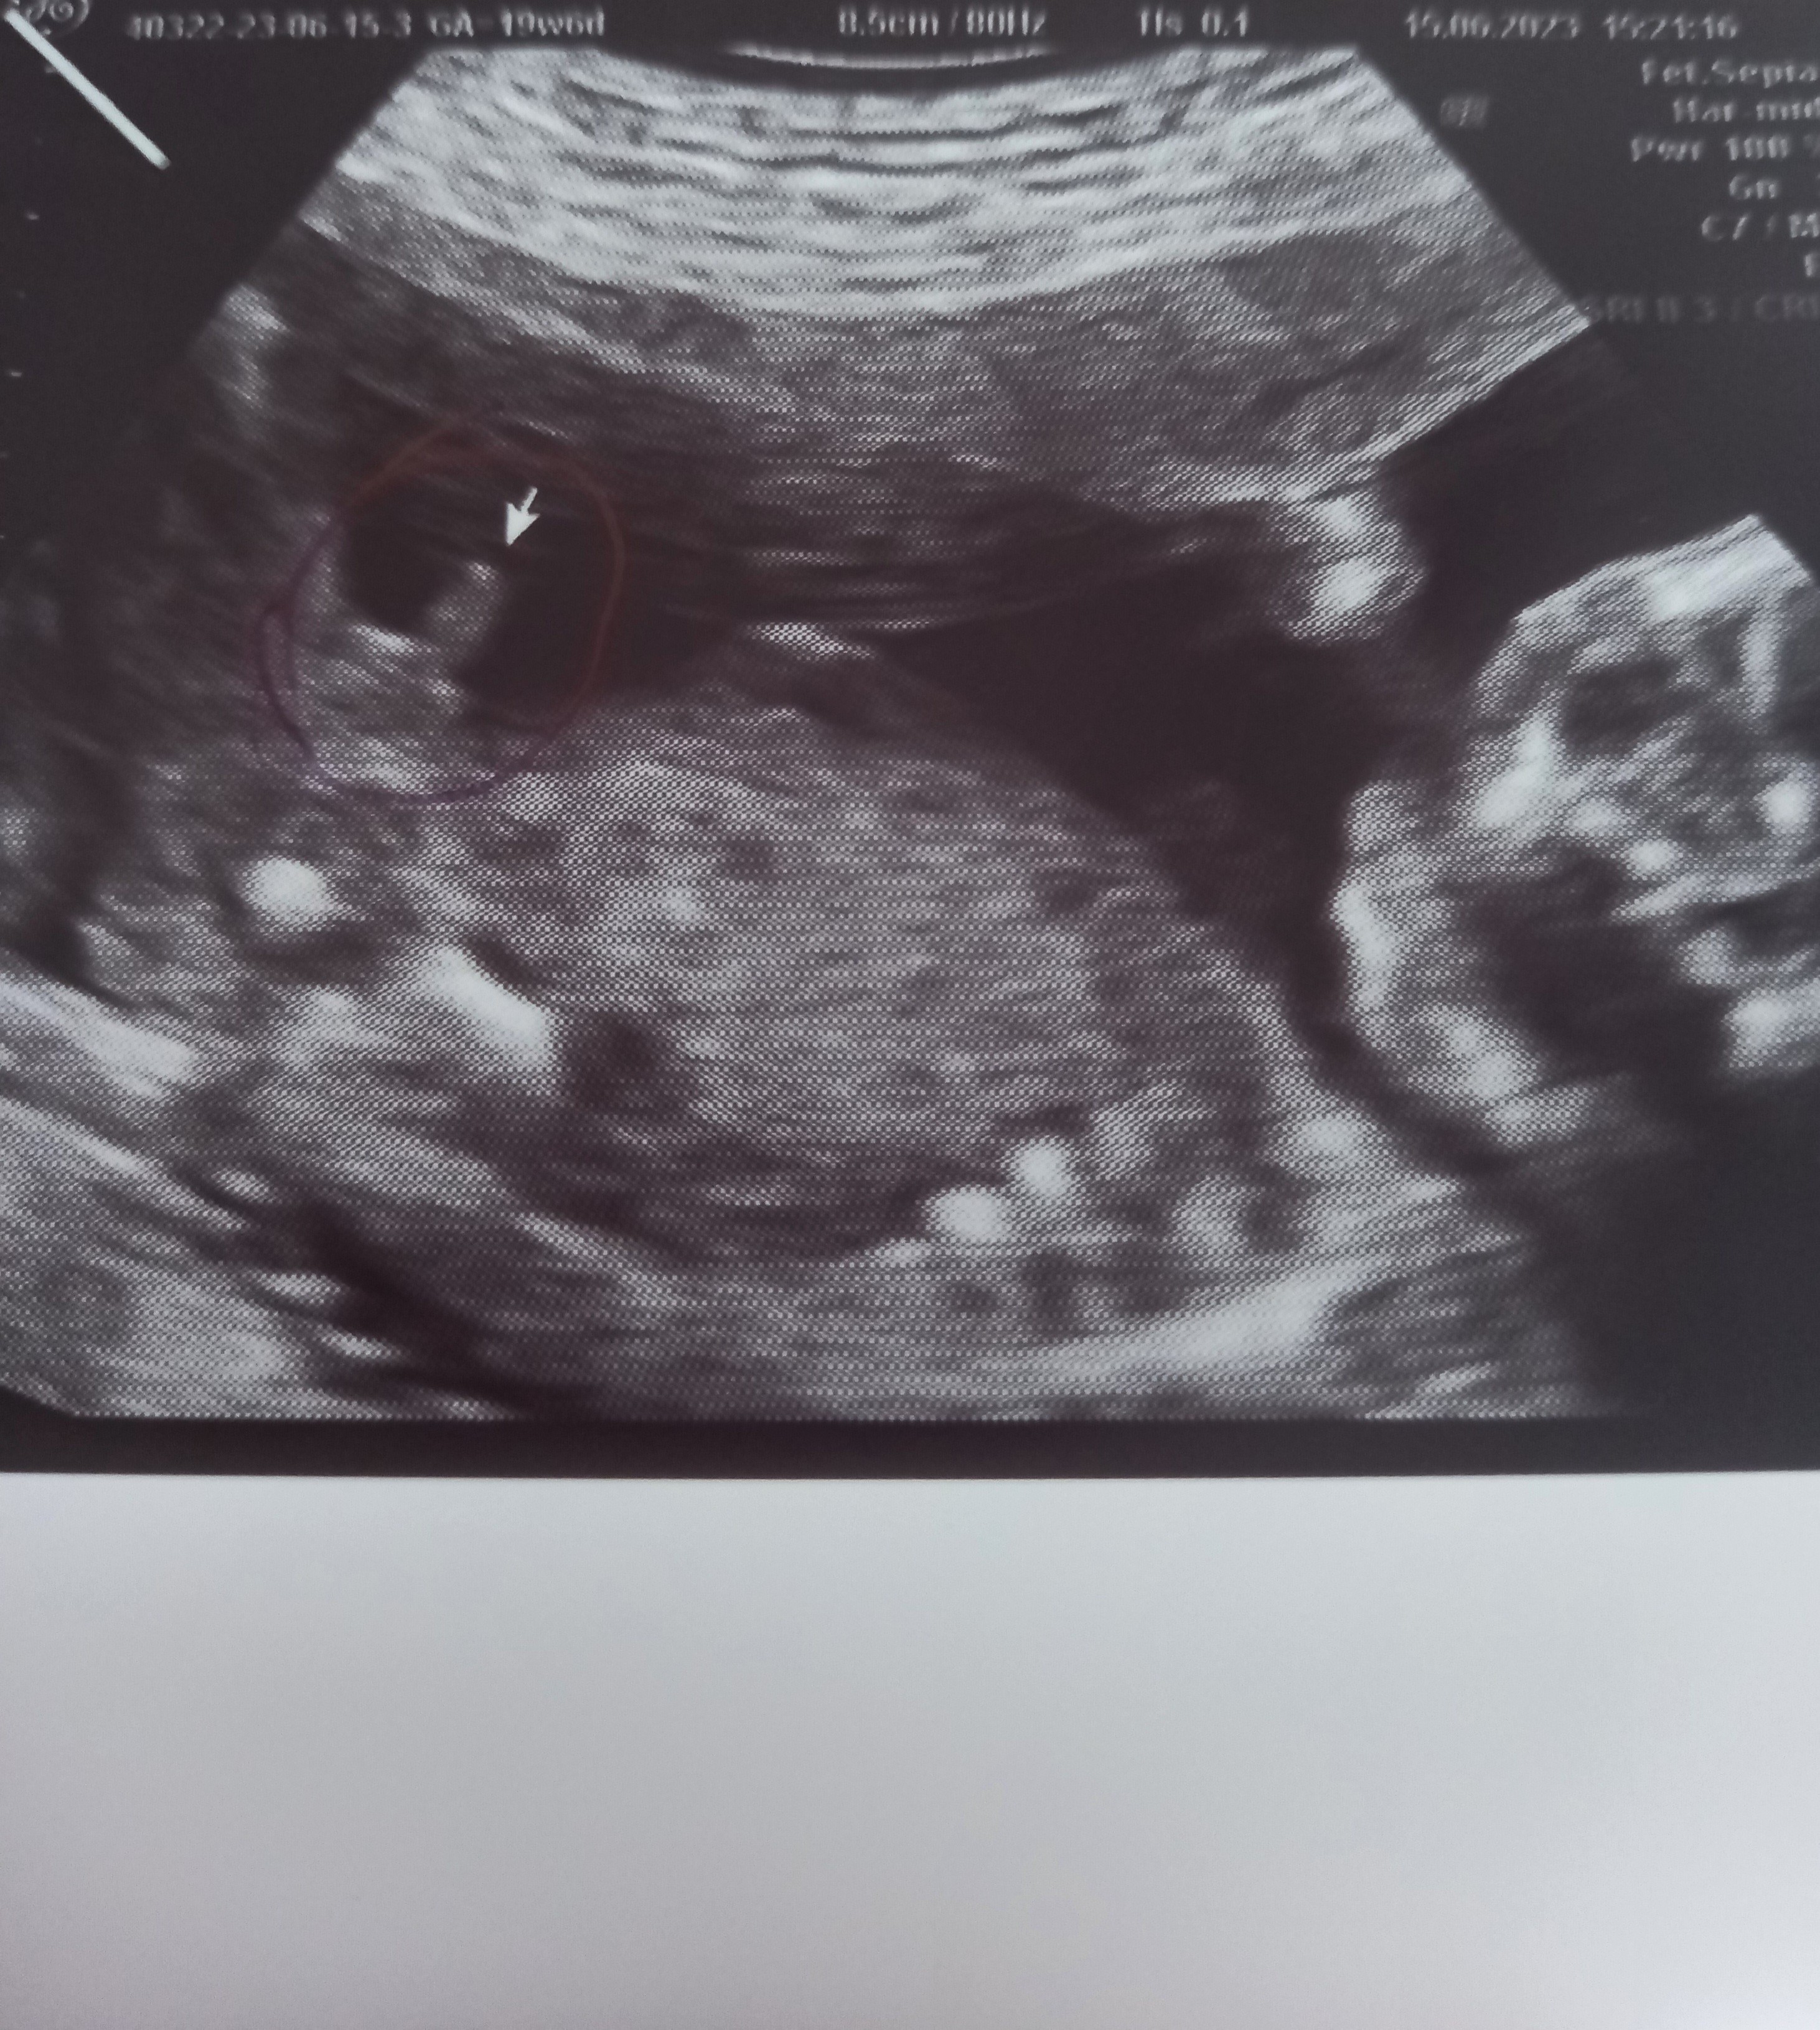

Wyrostek płciowy na usg

Dzięki za odpowiedź 🙃🙃 wg mnie wyrostek u mojego to może być ta biała kreska 🙉 zobaczymy najważniejsze by było zdrowe ale człowiek już by chciał coś kupić dedykowanego pod płeć 🥹

Załączniki

• 20230615_154942.jpg

20230615_154942.jpg

1,3 MB · Wyświetleń: 945

• 20230615_154938.jpg

20230615_154938.jpg

1,6 MB · Wyświetleń: 949